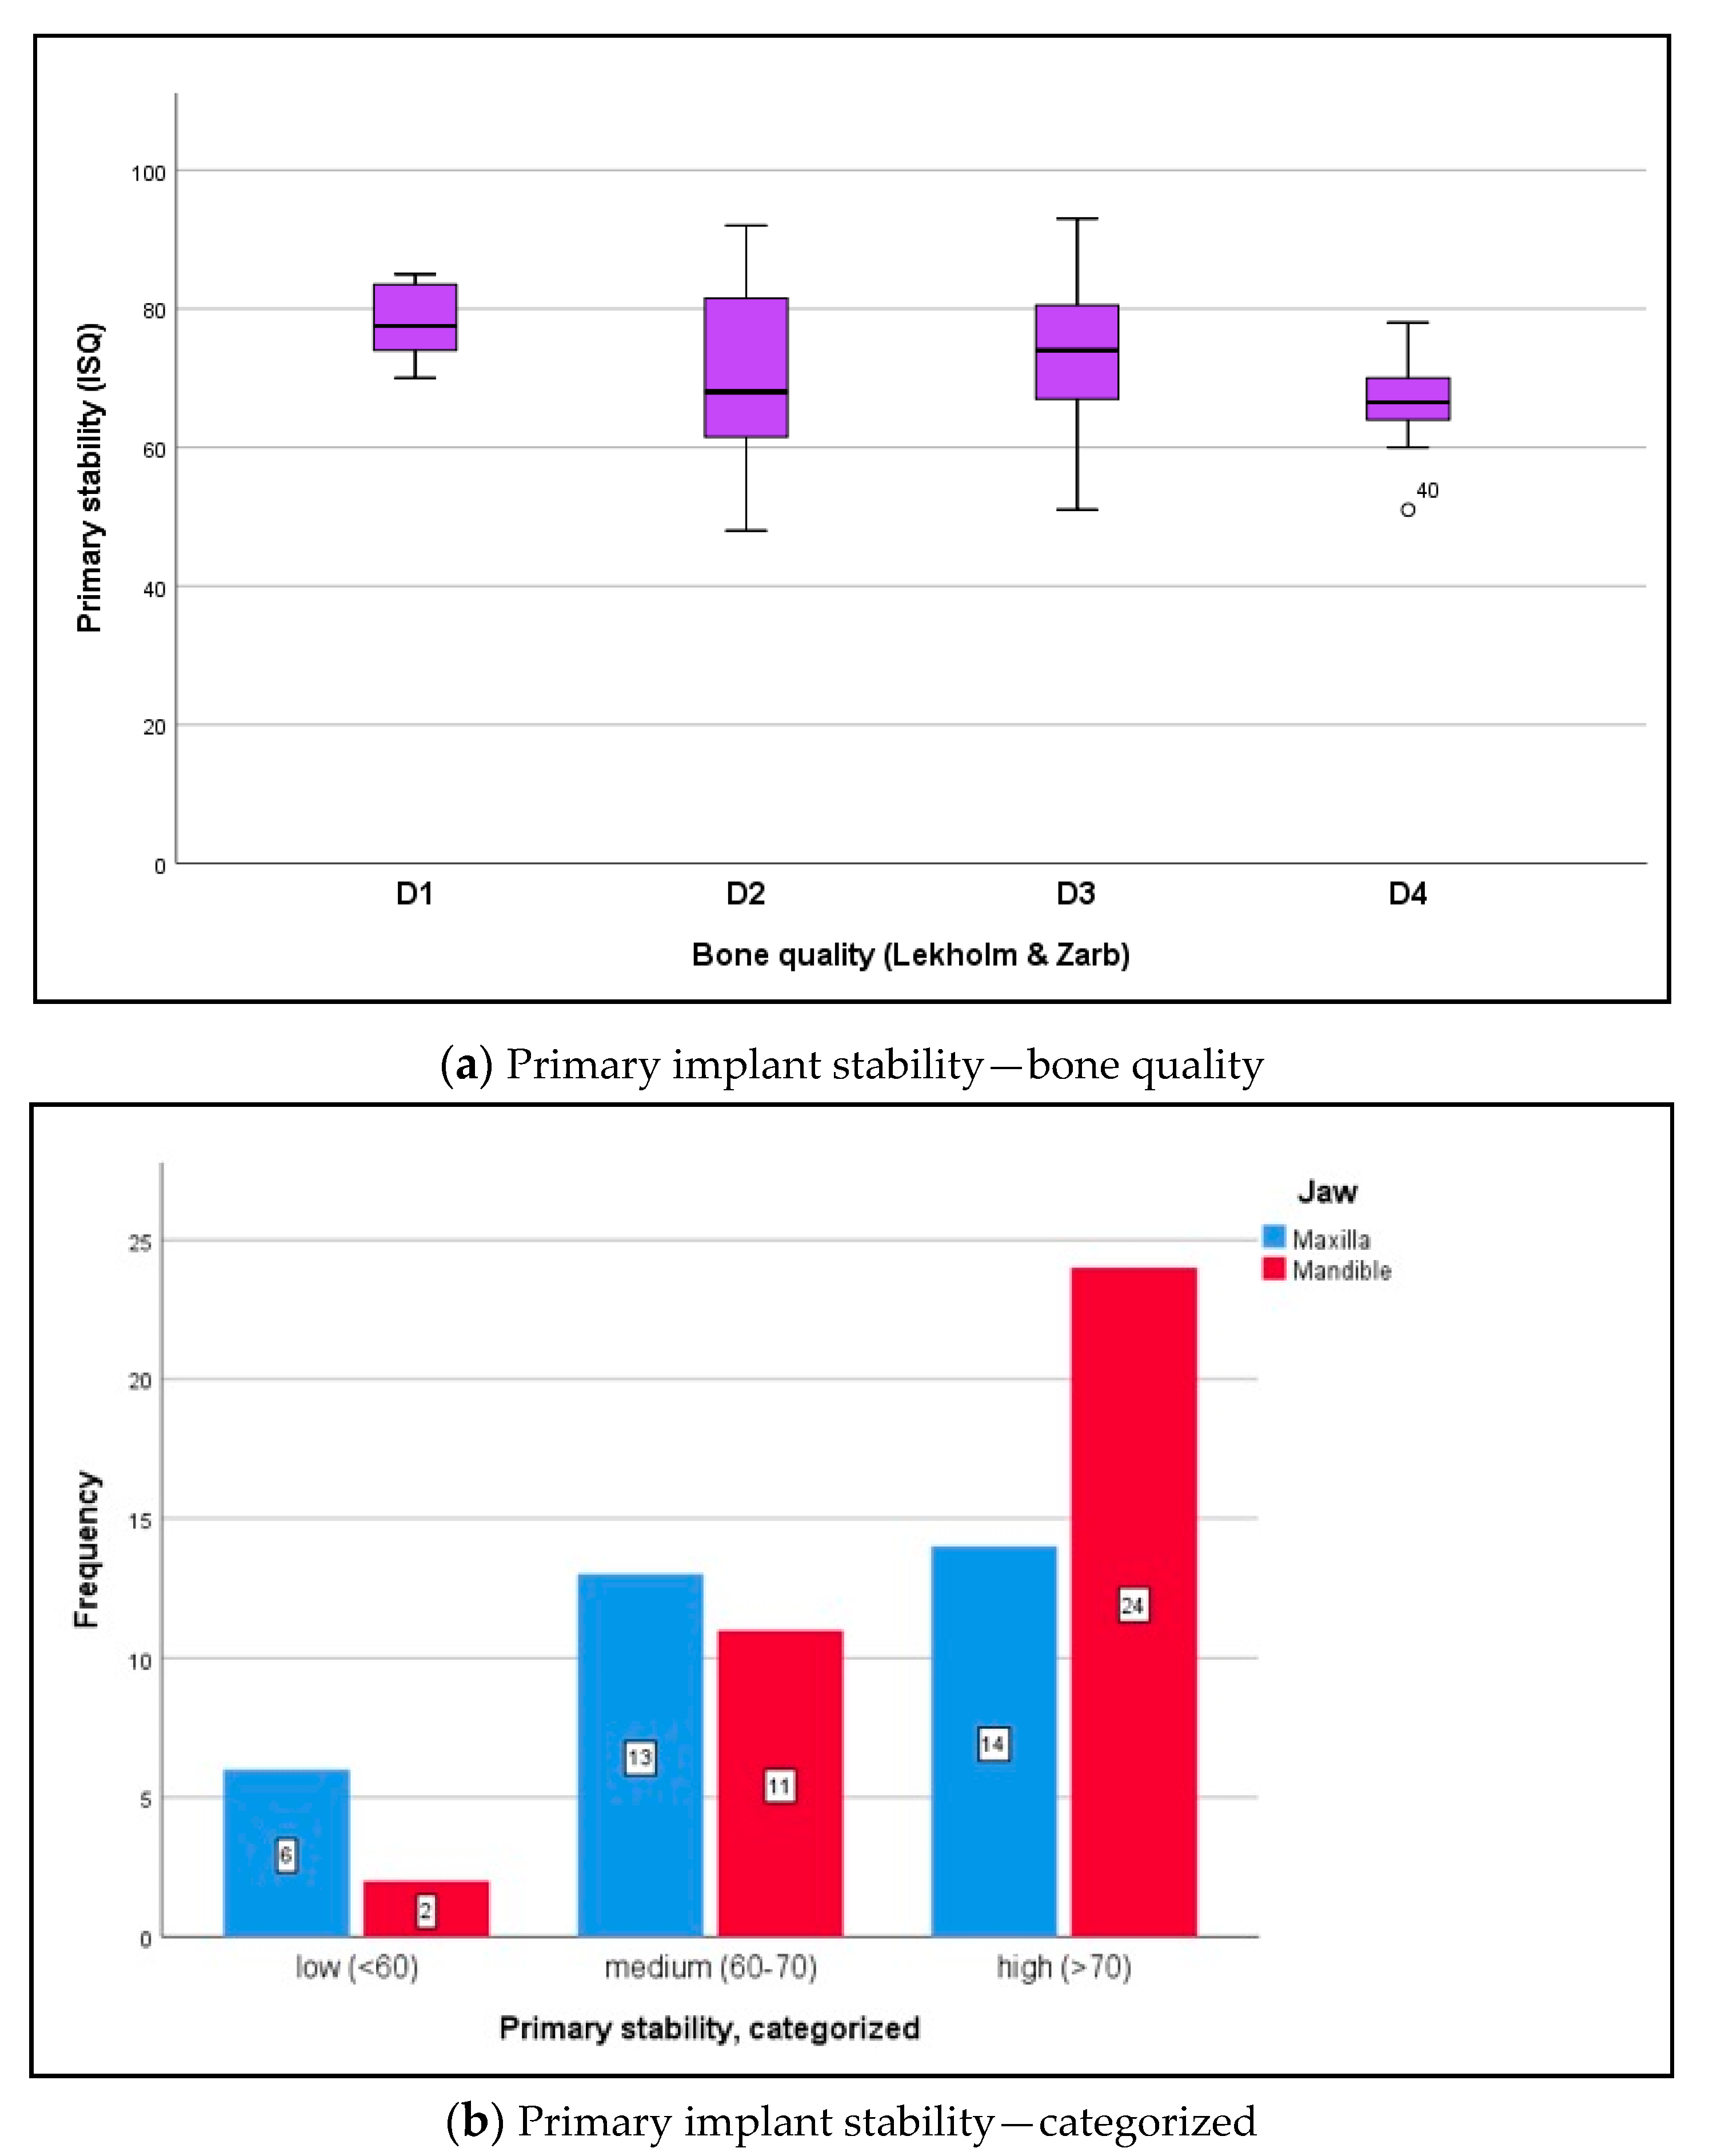

3.3. Biomechanical Implant Stability

4.2. Implant Stability under Difficult Conditions